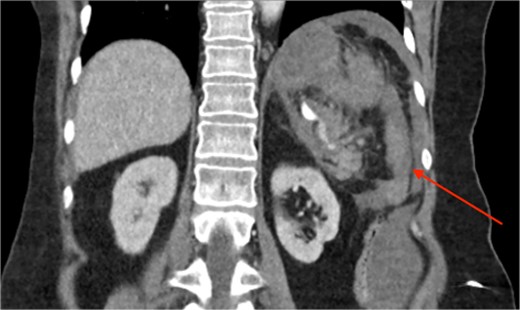

Triple-phase computed tomography (CT) of the abdomen and pelvis revealed a sizeable acute haematoma in the left upper abdomen, below the gastric fundus and body, alongside the pancreatic tail and splenic hilum, extending amongst the proximal small bowel mesentery and into the left subphrenic space. The origin of the haemorrhage appeared to arise from the left upper quadrant. There was a pseudoaneurysm in close proximity to the pancreatic tail and splenic hilum, apparently arising from the adjacent distal splenic artery. CT scan did show local contrast extravasation into the haematoma, as mentioned above (Figs 1–3).

CT of the abdomen and pelvis, coronal plane, arterial phase. Large intraabdominal haematoma in the left upper quadrant.